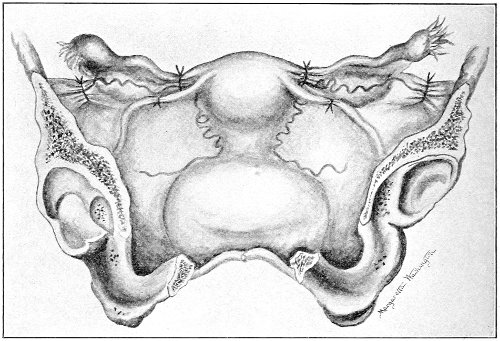

An accurate knowledge of the anatomy and mechanism of the female perineum is essential to an understanding of the nature and treatment of injuries to this structure. The anatomical structures lying between the anus behind and the symphysis pubis in front are those that most directly interest the gynecologist. Proceeding from 57 below upward, we find the following structures lying in superimposed planes: the skin, the superficial fascia, the deep layer of the superficial fascia, the transversus perinæi and the sphincter vaginæ muscles, the anterior layer of the triangular ligament, the posterior layer of the triangular ligament, the levator ani muscle (Fig. 19).

Fig. 18, A.—Superficial structures of the female perineum (Weisse).

The vagina passes through these structures. They surround and support the ostium vaginæ as the fascia and muscles surround and support the opening of the rectum or the anus. The muscles and fasciæ are attached in the median line between the anus and the vagina, and therefore this part of the body, which is called the perineum, is supported or maintained in its 58 proper position by these various structures. The transversus perinæi arises from the ramus of the ischium and is inserted in the perineum. The bulbo-cavernosus, or sphincter vaginæ, arises in the perineum and is inserted in and about the clitoris. The inner fibers of the levator ani arise from the symphysis pubis and are inserted in the perineum and the lower part of the vagina (Fig. 20). When these muscles contract, their action, therefore, is to draw the perineum upward and forward. At the same time the anus is drawn upward and forward, and so also is the posterior margin of the ostium vaginæ and the lower portion of the posterior vaginal wall.

The vagina has no circular sphincter like the anus, but 59 the vaginal month is kept closed by the action of the transversus perinæi, sphincter vaginæ, and levator ani muscles, which draw the perineum forward, and thus keep the posterior vaginal wall in apposition with the anterior wall.

Fig. 21.—Muscular floor of the pelvis seen from above.

This sling of muscles and fascia, which surrounds and supports the opening of the vagina, may readily be felt in the nulliparous woman by introducing the finger in the vagina and pressing backward and outward toward the ischio-rectal fossa. We then feel plainly, immediately within the ostium vaginæ, a firm resisting band of tissue, apparently about half an inch broad, embracing the posterior portion of the lower vagina. This band is formed by the inner edges of the various muscles and planes of fascia that have been described.